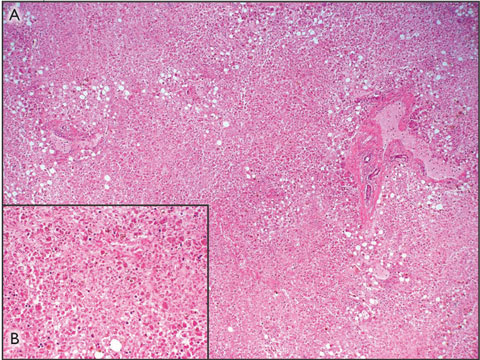

The patient was subsequently listed for liver transplantation, but died before a suitable donor became available. Postmortem examination confirmed that the cause of death was multisystem organ failure secondary to acute liver failure associated with paracetamol toxicity. The liver weighed 0.786 kg (normal weight in women, 1.2–1.4 kg), and the capsule appeared wrinkled. Histological assessment of the liver revealed a pattern of massive panlobular necrosis, with some mild fatty changes associated with preserved hepatocytes adjacent to portal tracts. The sinusoids contained increased numbers of inflammatory cells (Box 1).